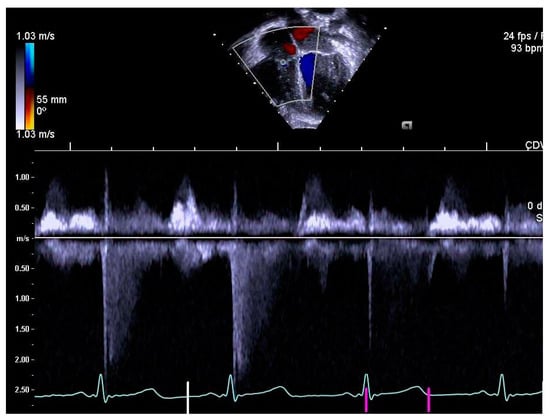

2.4. Determination of Right Heart Outcome Variables

3.4. Pulmonary Artery Diameters

3.5. Right Heart Systolic and Diastolic Functions